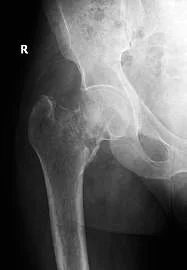

Avulsion Fractures

- Part of bone separated by forceful sudden resisted muscle action

- Caused by ligament or tendon pull on bone

- Part of bone avulsed – bone weaker than tendon/ligament